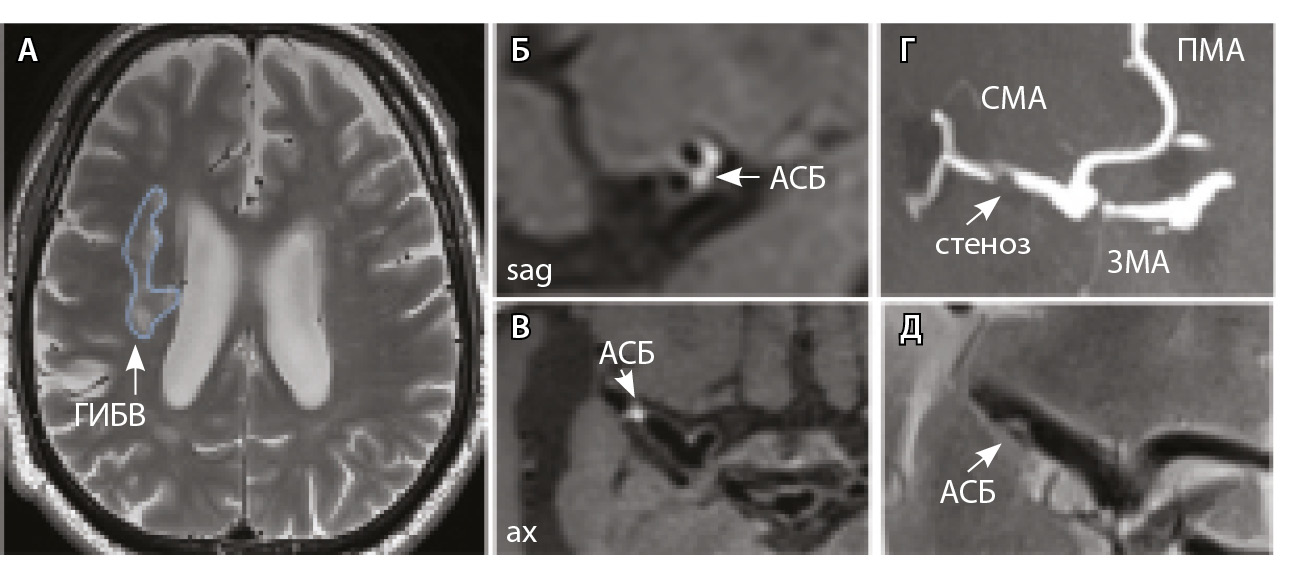

У всех включенных в исследование пациентов определялись атеросклеротические изменения брахиоцефальных артерий, в том числе на интракраниальном уровне, разной степени выраженности. У 9 больных отмечались признаки отрицательного ремоделирования артерий – выявление АСБ в стенке артерий, без сужения их просвета. Присутствовали изменения вещества головного мозга: инфаркты, в том числе лакунарные, – в 17 (58%) наблюдениях; МРТ-признаки церебральной микроангиопатии (ЦМА) – у 20 (68%) пациентов, среди них со степенью выраженности (F) по шкале Fazekas: F1 – у 7 (35%), F2 – у 4 (20%) (рис. 3), F3 – у 9 (45%) (рис. 4) [27]. Средние, большие и обширные инфаркты мозга зарегистрированы у 6 (20%) больных. Для количественной оценки изменений АСБ выбирался наиболее пораженный участок артерий (за исключением окклюзии): в 12 (41,4%) случаях это был интракраниальный сегмент внутренней сонной артерии (ВСА), в 10 (34,5%) – средней мозговой артерии (СМА), в 6 (20,7%) – базилярной артерии (БА), в 1 (3,4%) – задней мозговой артерии (ЗМА) (см. табл. 1).

Рис. 4. Пациент К., 69 лет, с признаками церебральной микроангиопатии (F2 по шкале Fazekas) и атеросклерозом интракраниальных артерий, с формированием гемодинамически значимого стеноза в сегменте М1 правой средней мозговой артерии (СМА): А – магнитно-резонансная томография (МРТ), режим Т2-взвешенного изображения: видны множественные сливные очаги гиперинтенсивности белого вещества (ГИБВ); Б, В – МРТ сосудистой стенки, режим T1-TSE-db-FS после контрастного усиления: в сегменте М1 правой СМА визуализируется эксцентричная атеросклеротическая бляшка (АСБ), интенсивно накапливающая контрастный препарат; Г – трехмерная магнитно-резонансная времяпролетная (3D ToF) ангиография: виден стеноз правой СМА в сегменте М1; Д – режим HR Т2-TSE: видна АСБ в сегменте М1 правой СМА; ax – аксиальная, sag – сагиттальная плоскости; ЗМА – задняя мозговая артерия; ПМА – передняя мозговая артерия